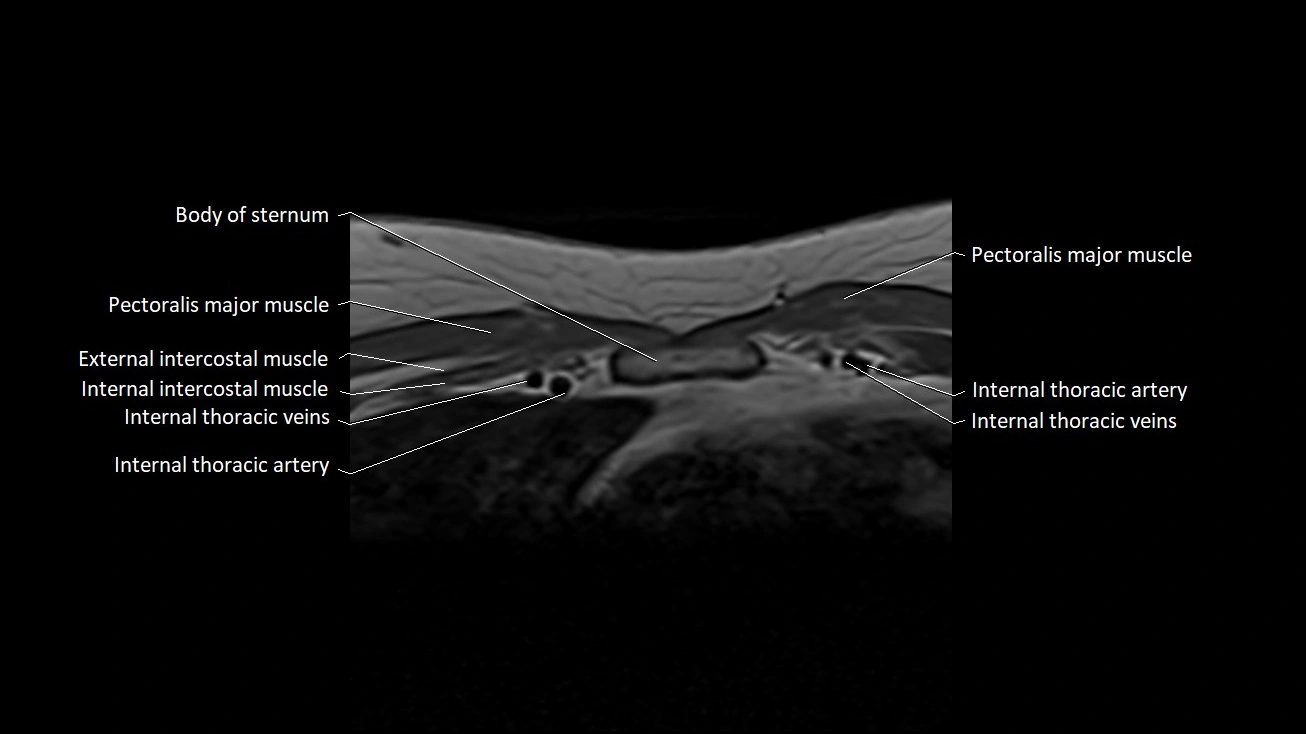

MRI Appearance

T1-weighted images

• Ligament appears as a low-signal (dark) linear band on the anterior aspect of the SC joint.

• Surrounding fat appears bright, providing contrast with the ligament.

• The clavicle and manubrium show normal cortical low signal with bright fatty marrow internally.

T2-weighted images

• Ligament remains low signal, darker than adjacent soft tissues.

• Articular disc and capsule appear as low-signal structures.

• Joint space fluid (if present physiologically) appears bright.

STIR

• Ligament maintains low-to-intermediate dark signal.

• Excellent for outlining adjacent soft-tissue planes due to fat suppression.

• Surrounding muscles and fascia demonstrate expected intermediate signal.

T1 Fat-Sat Post-Contrast

• Normal ligament shows no intrinsic enhancement, remaining uniformly low signal.

• Capsule may show minimal thin enhancement due to vascularized synovium.

• Fat suppression highlights the ligament’s dark, non-enhancing fibers.